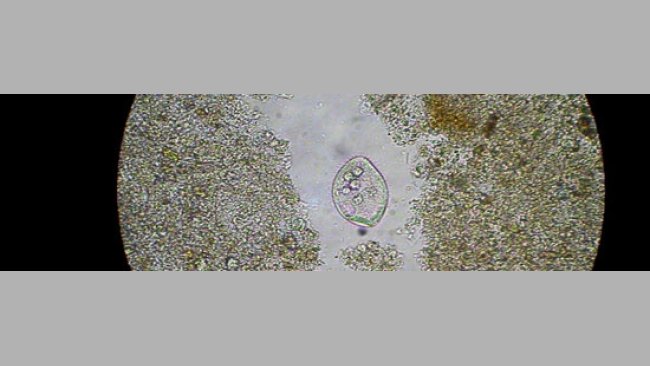

Caso clínico: Balantidiosis

Durante el mes de septiembre de 2001, el ganadero advirtió de la presencia de diarrea en cerdos de entre 9 a 10 semanas de vida alojados en una única sala de destete.